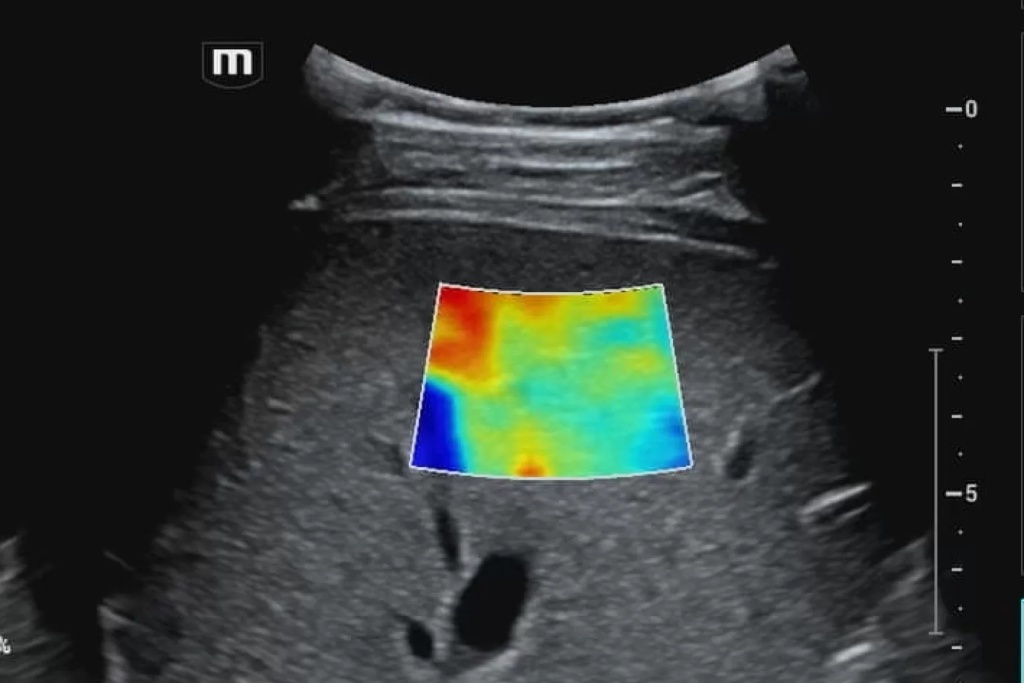

Особенности использования режима тканевой гармоники в медицинской диагностике

Режим тканевой гармоники имеет ряд особенностей, которые отличают его от традиционных режимов УЗИ:

1. Улучшенное контрастное разрешение. Это означает, что на изображениях, полученных в режиме тканевой гармоники, различные ткани и структуры более четко различимы. Это связано с тем, что в режиме тканевой гармоники подавляются артефакты, которые могут маскировать мелкие детали.

2. Уменьшение артефактов. Артефакты — это искажения изображения, которые могут затруднять диагностику. Режим тканевой гармоники позволяет уменьшить количество артефактов, что улучшает качество изображения.

3. Увеличение глубины проникновения. Режим тканевой гармоники позволяет получать более четкие изображения органов, расположенных глубоко в теле. Это связано с тем, что в режиме тканевой гармоники ультразвуковые волны поглощаются тканями меньше, чем в традиционных режимах УЗИ.

Режим тканевой гармоники — это современная технология, которая значительно улучшает качество УЗИ изображений. Эта технология широко используется в различных областях медицины, что позволяет врачам получать более точную и достоверную информацию о состоянии здоровья пациентов.